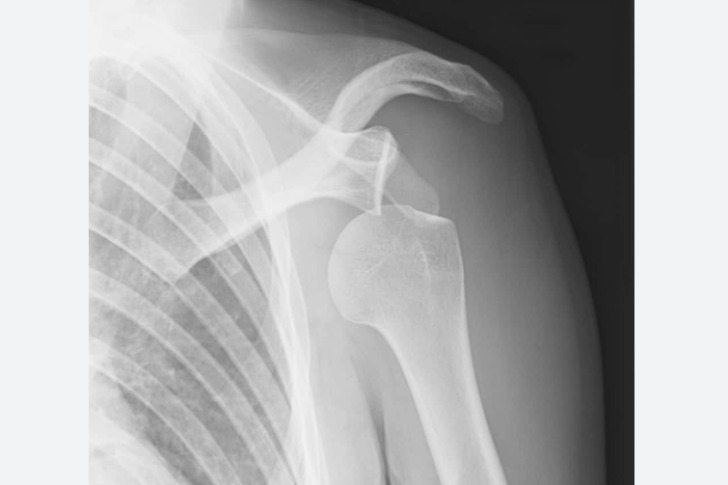

I once dislocated my shoulder by rolling my ankle. My ankle was fine, the shoulder not so much. I have hypermobility, which results in slack tendons in my ankles and shoulder joints, among other things. This makes me more prone to rolling my ankle, but it’s rare to actually hurt it, because the tendons can stretch enough that my ankle bone can be basically sitting on the ground. However, the jerking motion of the ankle roll was enough to pop the joint out of my shoulder socket.